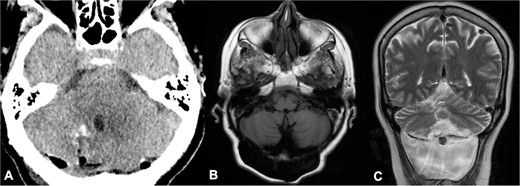

A 66-year-old woman presented with ataxia and dysmetria. She had a past medical history of hydrocephalus and seizures secondary to neurocysticercosis that merited medical management with a 30-day protocol of albendazole administration at 15 mg/kg/d and placement of a ventriculoperitoneal shunt (Fig. 1). Over the year before admission, brain imaging revealed multiple and increasing cystic lesions in the right cerebellar hemisphere (Fig. 2A–C). Besides, a follow-up brain MRI with contrast revealed multiple contrast-enhancing cysts compressing the fourth ventricle, perilesional edema, and an extra ventricular component next to the cerebellar tentorium (Fig. 2D–F).

Initial brain CT revealed multiple calcified cysts with ventriculomegaly in the axial (A, C) and sagittal (B) views.